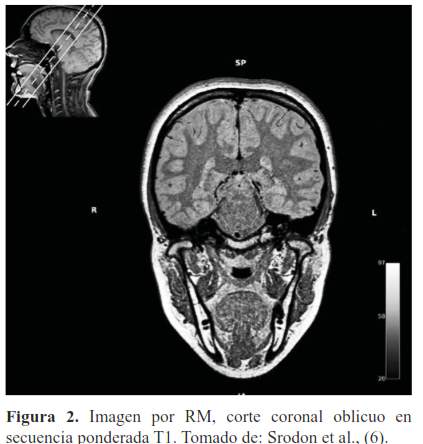

El T1 tiene que ver con el intercambio de energía térmica, realizado desde los protones al medio. Los protones entregan energía al medio para relajarse; cuando el medio está formado por liquido/agua es difícil para los protones liberar su energía porque las pequeñas moléculas de agua se mueven demasiado por lo que volverán lentamente al nivel de menor energía, a su alineación longitudinal, esto significa que los líquidos/agua tienen T1 largos (5), observándose hipointensos y la grasa se observa brillante o hiperintensa (figura 2).